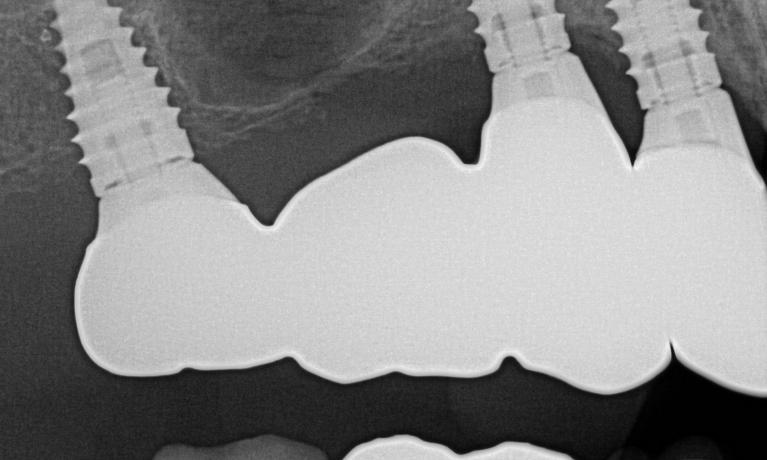

We take great pride in the services we perform in our office. We always try to not only meet your expectations, but we also try to exceed them. There are many types of services that we perform in our office, as well as others that we perform in coordination with highly skilled specialists. We have compiled a few examples of the treatments that we have performed. We are proud to say that these are the usual results our patients expect to see.

The photos are not retouched, nor are they taken by a professional photographer. These are just the routine treatment photos that we take and the results that we see every day. They are by no means a comprehensive catalog of the procedures that we perform. They are just a small sample of some of the results you can expect when you seek treatment in our office.